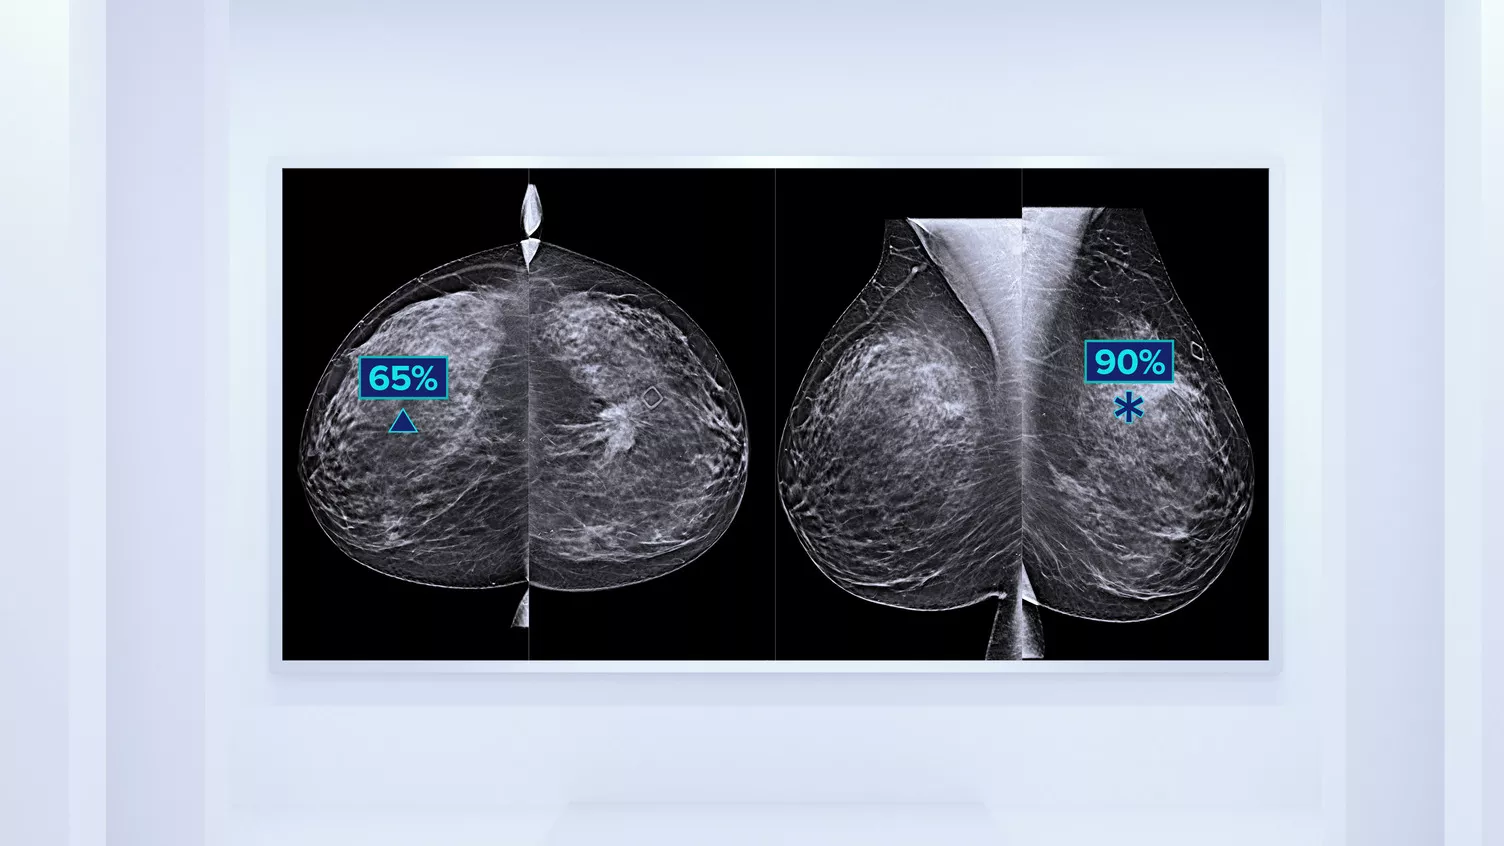

Better Risk Prediction

In addition to volume, pattern and texture of fibroglandular tissue may play just as an important role in mammographic cancer risk prediction.3-5 By analysing and categorising breast texture and pattern, our technology can deliver the accurate information you need to achieve more consistent and reliable scoring and confidently design patient-specific screening.

Objective machine learning algorithm that assigns breast density category based on analysis of breast tissue texture and patterns.